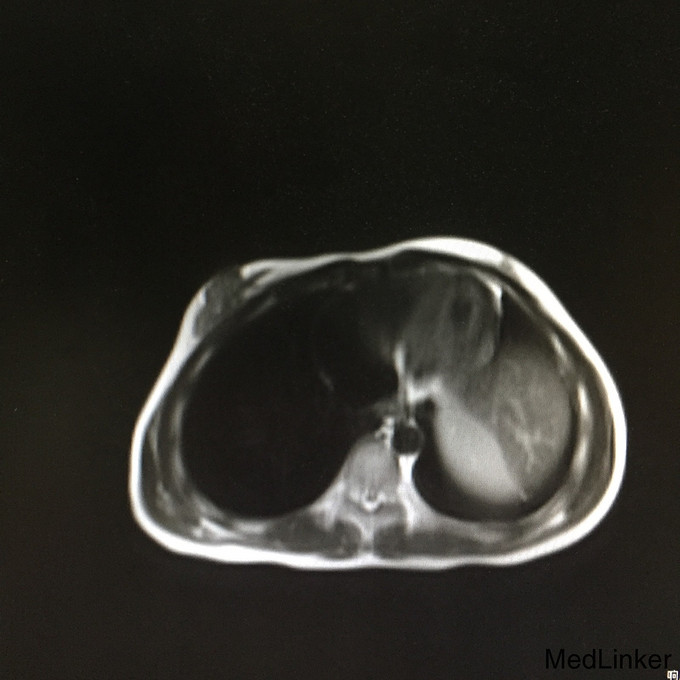

查体:生命体征平稳;双侧乳腺发育稍差。妇检:外阴呈女性生殖特征,阴蒂肥大,可见尿道开口;阴道外口可见,无性生活史,未内诊。肛查示子宫小,盆腔右侧可及包块。 辅查:2015-08-15妇科B超示:子宫小,左侧卵巢内未见明显卵泡结构;右侧附件区囊性肿块,待排畸胎瘤(43mm*30mm)。 2015-08-24查染色体示46XY,t(4;20)(q27;p13)。 2015-09-28我院查盆腔MR示双侧附件肿块,性质待定,考虑卵巢来源;阴茎发育短小,子宫小,符合双性畸形改变。

诊断:两性畸形 治疗:请我院资深超声科主任医师复查妇科B超示双侧两性母细胞瘤可能。查腹部MR:1.右侧附件区囊实性肿块,左侧附件区实性肿块,性质待定,考虑卵巢来源肿瘤。 2.阴茎发育短小,子宫稍小,符合双性畸形改变。 3.双侧肾脏及输尿管、膀胱MRI扫描未见异常。 4.上腹部MRI扫描未见异常。 请儿科教授会诊,46XY性发育障碍,意见:女性表型含Y染色体者发生性腺恶性肿瘤可能性大,建议腹腔镜性腺切除。查皮质醇8AM正常及ACTH 8AM,均正常。行腹腔镜下双侧性腺肿瘤切除术+双输卵管切除术。术中冰冻结果:良性。